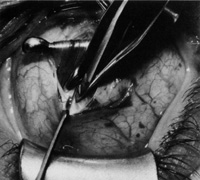

Step 3. Two double-armed 6-0 Vicryl sutures are used to secure each half of the muscle separately (Fig. 4). Both halves of the muscle are disinserted from the sclera (Fig. 5).

Fig. 4. Two double-armed 6-0 Vicryl sutures are used to secure each half of the muscle separately.

Fig. 5. Both halves of the muscle are disinserted from the sclera.